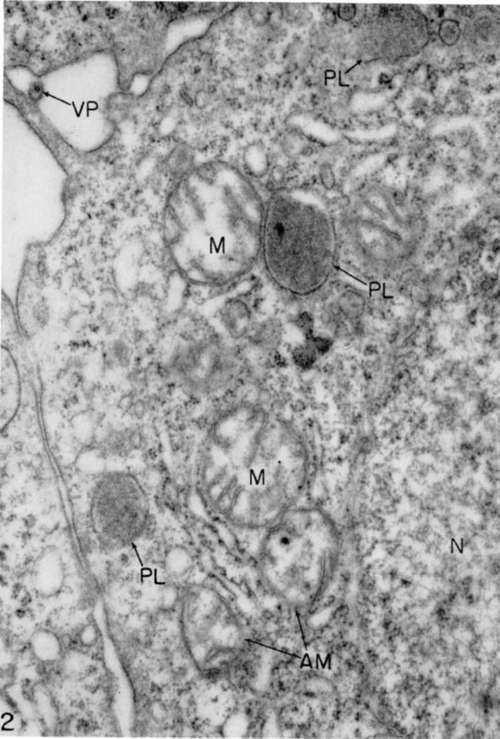

Figure 2. Myeloblast from same source as that of figure 1 after 2 hours in tissue culture in a growth-supporting medium. Mitochondria (M) are somewhat swollen, and two (AM) appear to be undergoing internal disorganization. Viroplasts (PL) occur frequently in sections of these cells. A virus particle (VP) lies outside cell. Structure of nucleus is shown at (N). X 48,000.